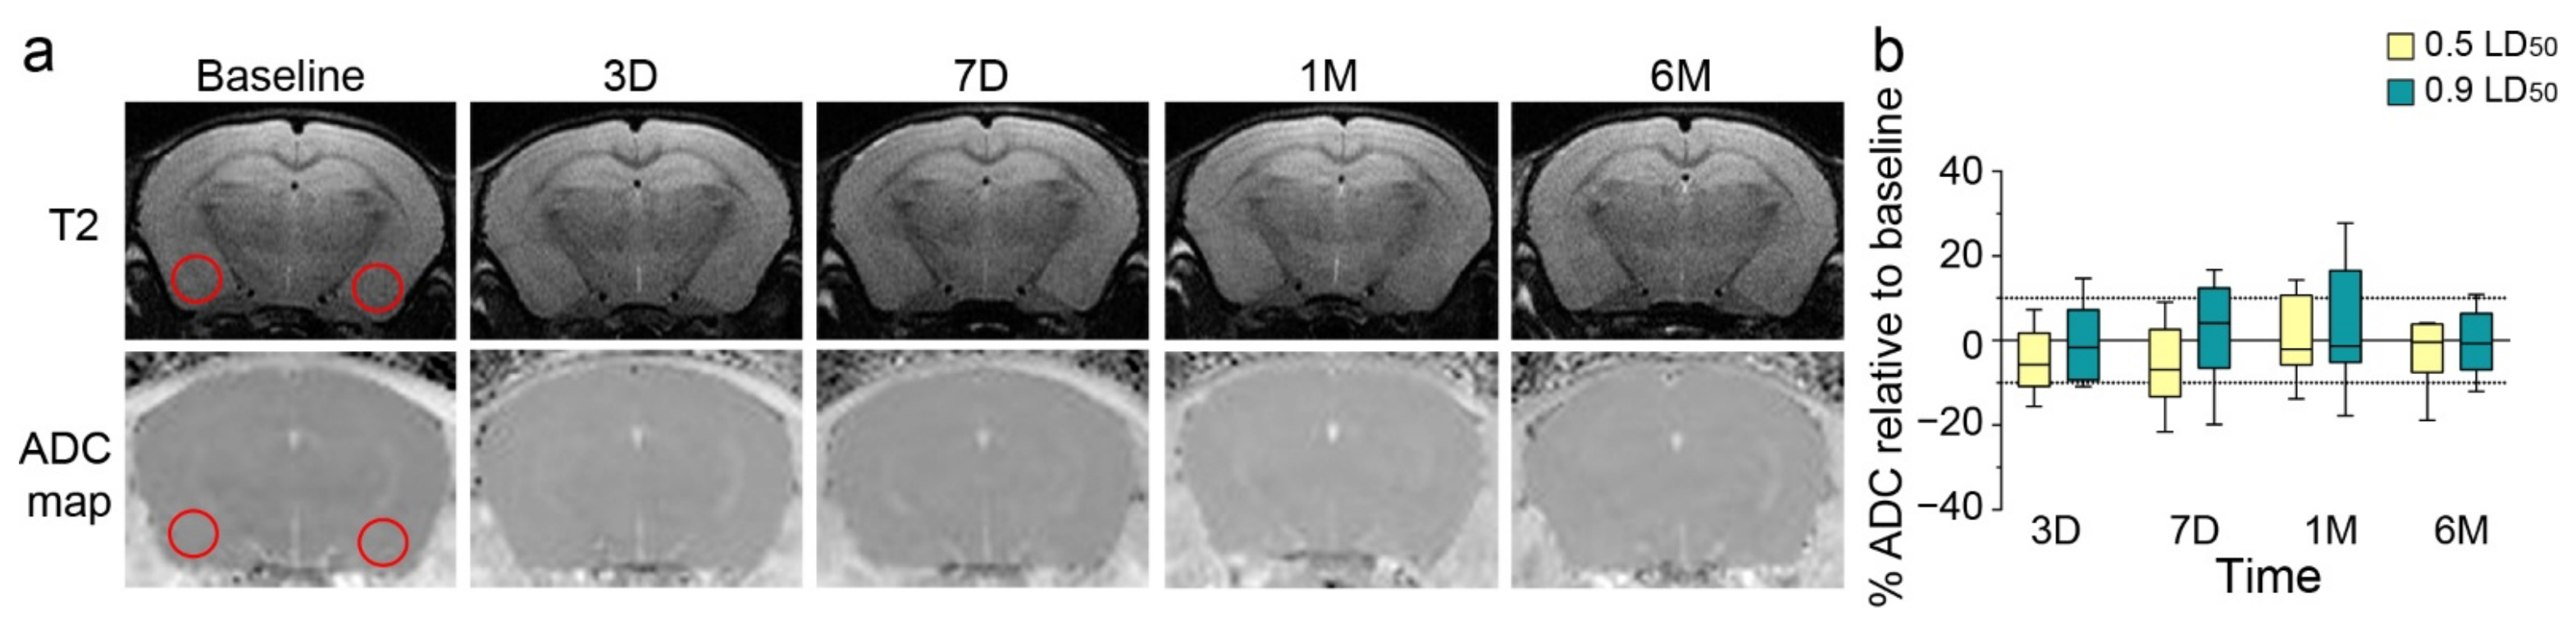

3.3. Longitudinal Imaging Examination and Long-Term Induced Inflammation

To explain these behavioral long-term modifications, we conducted MRI in parallel on 0.5 and 0.9 LD50 NIMP-exposed mice for 6 months to evaluate morphological modifications and brain edema after exposure. The image analysis did not show significant neuroanatomical changes using T2-weighted images or edema formation using ADC mapping on DWI images (Figure 3).

Figure 3.

NIMP exposure does not induce morphological modifications or brain edema in the amygdala/piriform cortex. (a) T2 images with the apparent diffusion coefficient (ADC) map of one representative NIMP-exposed mouse (0.9 LD50) at different timepoints: before intoxication (baseline), and 3 days, 7 days, 1 month and 6 months after NIMP exposure. Regions of interest used for analyses are shown with red circles. (b) The percentage of ADC normalized to the baseline as a function of different timepoints for NIMP-exposed animal groups [(0.5 LD50: −5.1 ± 2.7 at 3D; −6.0 ± 3.5 at 7D; 1.7 ± 3.9 at 1M and −2.9 ± 3.1 at 6M) and (0.9 LD50: −0.8 ± 3.1 at 3D; 2.1 ± 4.3 at 7D; 2.9 ± 5.2 at 1M and −0.5 ± 2.7 at 6M)]. Statistical analyses were conducted by mixed-effects model (REML) analysis (FTime = 0.89, p = 0.44; FDose = 1.5, p = 0.24; FTimexDose = 0.36, p = 0.78) (n = 7 to 9 per group).

The amygdala is the primary brain region involved in anxiety behavior [41,42] and is one of the main brain regions to be particularly affected by NA exposure [43,44,45]. Neuronal hyperexcitability has been noted in the basolateral amygdala following exposure to a high dose of soman due to a decrease in GABAergic inhibition in this area [35,36]. A slow recovery in AChE activity coupled to a loss of GABAergic neurons may explain this hyperactivity and the development of anxiety-like behavior [35,36]. However, the low doses of NIMP used in our study did not induce any observable neuropathologies at any timepoint studied. This result is consistent with our previous study [17] and with other animal models exposed to a low dose of NA [15,46]. Furthermore, no anatomical volume modification of the amygdala was observed in our model at any timepoint studied, suggesting that neither cell loss nor swelling was induced after the low-dose exposure to NIMP. The amygdala is particularly sensitive to stress, which could be reflected by an increase in inflammatory cytokines leading to its enlargement [41,47].